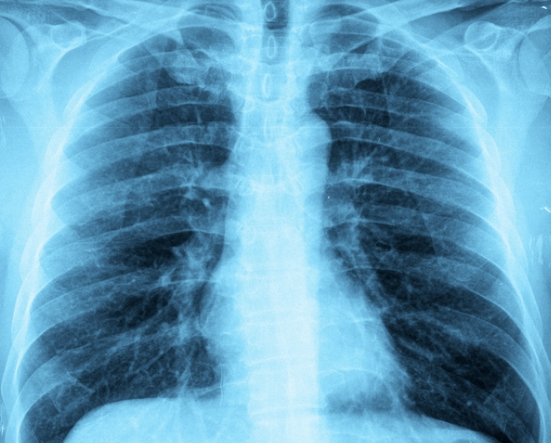

Gözle görülebilir bir hastalık çeşidi olan ve birçok nedenden dolayı ortaya çıkabilen akciğer lekesi rahatsızlığı nedir? Üst solunum yollarıyla vücuda girebilen mikroplar nedeniyle meydana gelen bu rahatsızlığın tedavisi nedir? İşte cevabı...

Birçok nedenden dolayı ortaya çıkabilen akciğer lekesi gözle görülebilir bir hastalık çeşididir. Genellikle üst solumun yolu ile vücuda giren ve ciğerlere yerleşen mikroplar nedeniyle yaşanır. En tehlikeli olduğu durum ise kanser veya mantar gibi rahatsızlıkların belirtisi de olabilir. Yaygın görülen bu rahatsızlık için öncelikle röntgen ve tomografi çekilmelidir. Uzman bu süreçten sonra leke tespit ettiğinde detaylı tetkiklerle ciddi olup olmadığına dair araştırma yapar.

NEDEN OLUŞUR? En yaygın nedenlerinden biri üst solunum enfeksiyonlarıdır. Bu enfeksiyon virüsleri akciğer zarında iltihaplanmaya neden olur. Zatürre ve bronşit gibi hastalıkların virüsleri de akciğerde lekelenmeye neden olur. Kanserli hücrelerin akciğer zarında birleşip tümör oluşturması da akciğer lekelenmesinin en tehlikeli boyutudur. Bu durum genellikle kafein, sigara ve bağışıklık sistemi çok zayıf olan kişilerde görülür.

Hamartomlar lipomlar ve kapsüller içerisinde büyüyen yağ hücreleridir. Bunlar bazı besinlerden dolayı ortaya çıkar. Kanserli olmayan oluşumlar olmasına rağmen akciğerde ciddi sağlık sorunlarına neden olur.

TEDAVİSİ NEDİR? Kanserli olan lekelenmeler ciddi boyutlara ulaşmadan engellenmesi için erken tedavi önemlidir. İyi huylu akciğer lekelenmesinde bile erken tedaviye başlanılmadığında kalıcı hasarlar meydana gelir. Enfeksiyondan kaynaklanan lekelenmelere uzmanlar genellikle antibiyotik tedavisi uygular.